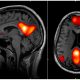

Beyindeki sinirsel iletimin büyük oranda elektriksel bir biçimde sağlanması, keşfedildiği günden bu yana ilgi çekici bir konu oldu. 2000'li yılların başından itibaren bilim insanları "beynin elektriksel yapısına müdahale edilerek beyin hastalıklarının iyileştirilebileceğine" dair düşünceyi sistematik bir biçimde denemeye koyuldular. Beynin elektriksel yapısına müdahale etme yöntemi olarak son döne...

"Mutlu Olma Sanatı" isimli kitabında insanın yaratıcı fikirler ortaya koyması için boş durmaya ve monotonluğa ihtiyacı olduğunu iddia eder. Gerçekten de birçoğumuz hayatımızı değiştiren bazı fikirlerin aklımıza bomboş durduğumuz anlarda geldiğini deneyimlemişizdir. Peki gözümüzü kapatıp dinlenmek için uzandığımızda ya da öylece bomboş uzaklara baktığımızda beynimizin içinde neler oluyor? Uzun yüzy...